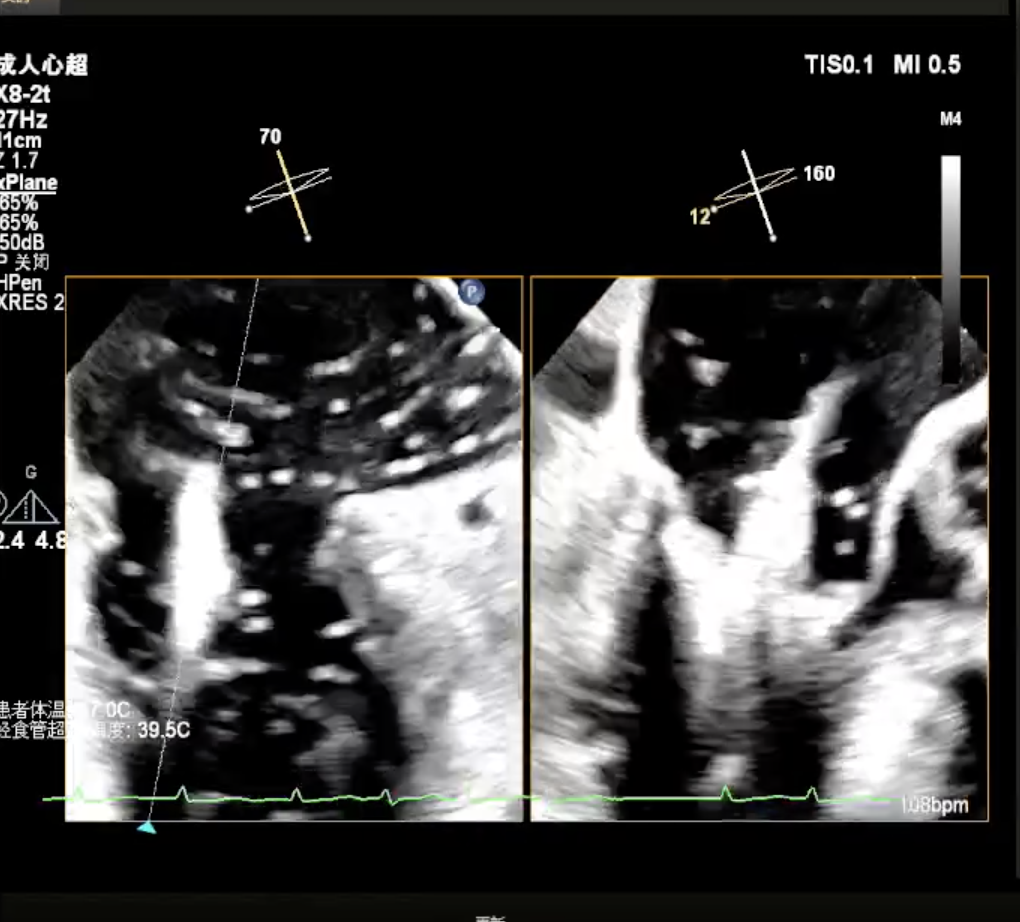

瓣上M/L和A/P调整瓣膜夹,在X-plane进行超声确认(视频),进行弹道路径检查;

3D指示下调整瓣膜夹朝向病变区域

确定瓣膜夹与病变区域垂直后,放下夹片;超声确认前叶后叶都夹合充分,3D检查瓣膜夹位置.

超声测量前瓣夹持长度0.91cm,后瓣夹持长度约1.14cm